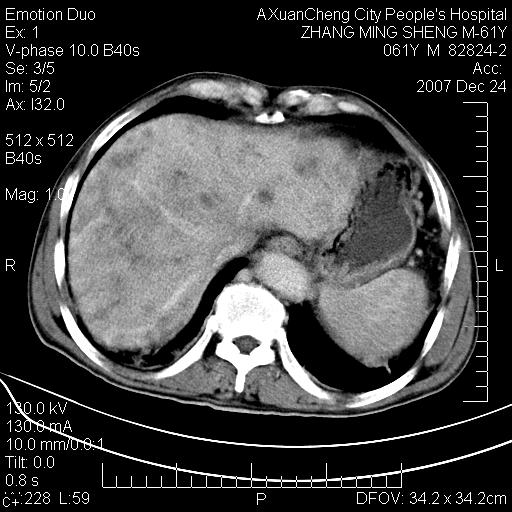

标题: CT11031:M61Y,胰腺占位

大家侃侃门静脉和胆管系统怎么回事,肝内转移?

胰腺癌肝转移

肝硬化,门脉高压,脾肿大;弥漫性肝癌,肝内、门脉、腹膜后淋巴结转移,肝内外胆管扩张,胰头区占位,建议mr检查

胰腺癌伴肝内转移;门脉、肠系膜上v癌栓形成。

考虑为:胰腺癌伴肝脏转移、腹膜后淋巴结转移,门静脉及肠系膜上静脉瘤栓形成。

胰体尾癌伴肝内转移,门静脉及肠系膜上静脉瘤栓形成.